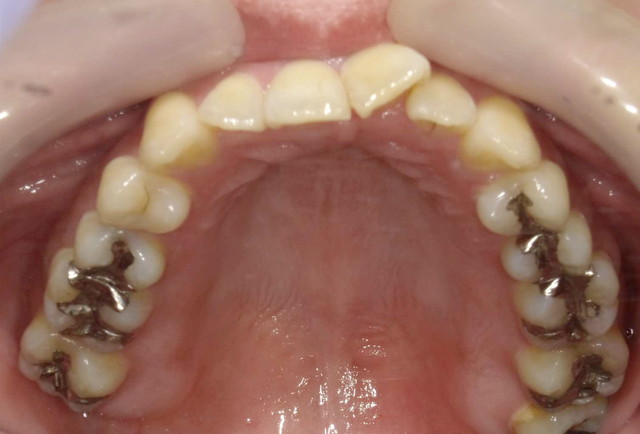

■治療前(上の歯)